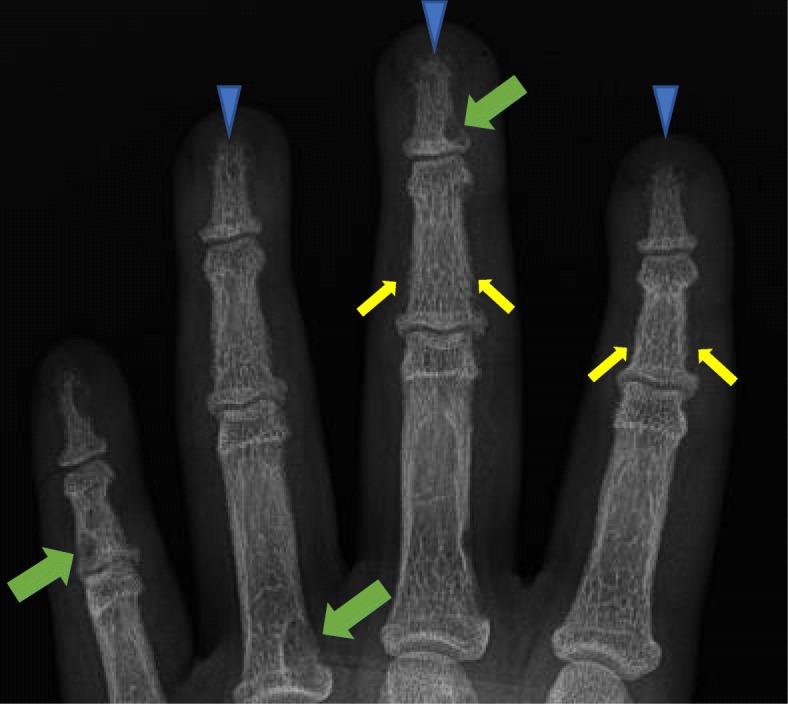

丢失的骨头:儿科风湿病医生所见的肢端骨溶解的鉴别诊断。

Lost bones: differential diagnosis of acro-osteolysis seen by the pediatric rheumatologist.

Acro-osteolysis is a radiographic finding which refers to bone resorption of the distal phalanges. Acro-osteolysis is associated with various conditions and its presence should prompt the clinician to search for the underlying etiology. The aim of this review is to discuss disorders with which acro-osteolysis is associated and their distinguishing features, with a focus on the pediatric population.

Genetic disorders (particularly primary hypertrophic osteoarthropathy and skeletal dysplasias) and rheumatic diseases (particularly psoriatic arthritis and systemic sclerosis) are the most frequently encountered conditions associated with acro-osteolysis in children. Hyperparathyroidism, neuropathy, local trauma and thermal injury, and spinal dysraphism should also be included in the differential diagnosis.

Although acro-osteolysis is uncommon, its presence should prompt the clinician to consider a differential diagnosis based on clinical and radiographic features.